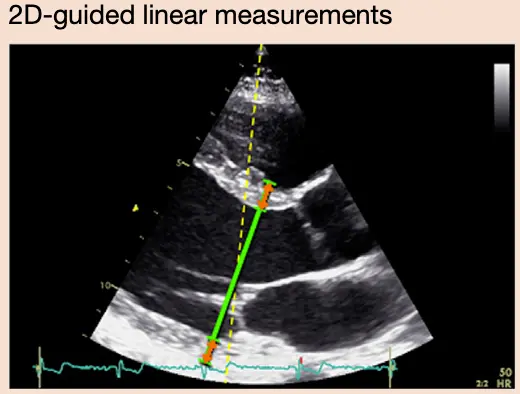

Linear Measurements

- Linear internal measurements of the left ventricle and its walls be performed in the parasternal long-axis view.

- Values should be carefully obtained perpendicular to the LV long axis and measured at or immediately below the level of the mitral valve leaflet tips.

- You want to be perpendicular to the LV long axis, i.e. in line with the flow of blood